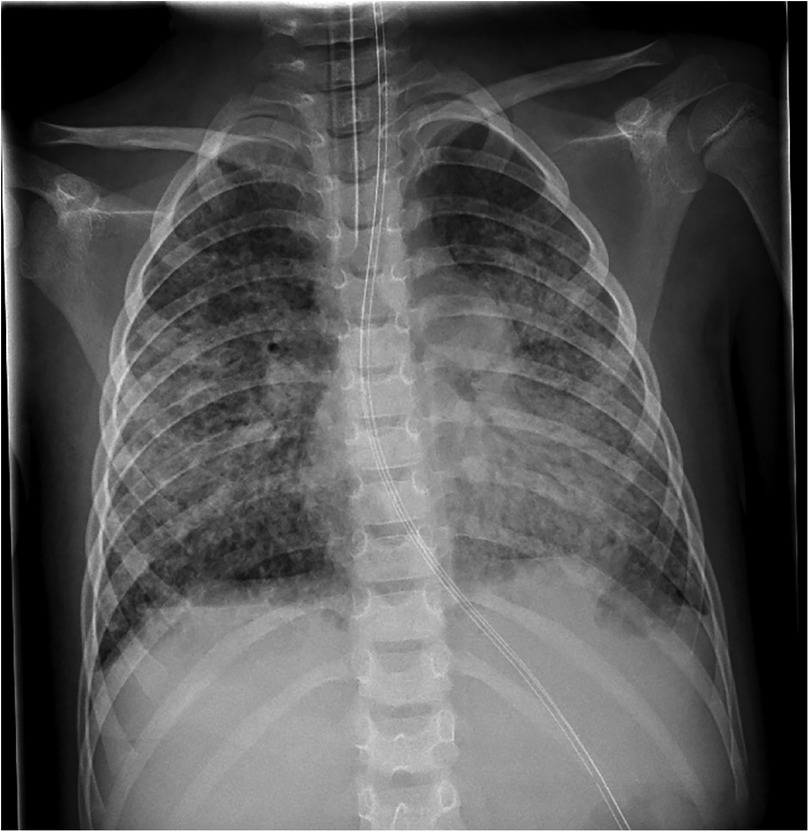

Veno-venous extracorporeal membrane oxygenation (VV-ECMO) is an established rescue therapy for severe pediatric ARDS, but prolonged support is rarely reported. We describe a previously healthy 6-year-old boy who developed Stevens-Johnson syndrome, complicated by progressive respiratory failure and severe ARDS. Despite maximal ventilation, oxygenation remained insufficient, and VV-ECMO was initiated on day 11 of illness. Cannulation was performed via jugular and femoral access, followed by lung-protective ventilation, repeated surfactant administration, corticosteroid therapy according to the Meduri protocol, and ACE inhibitor therapy. ECMO support was complicated by pulmonary fibrosis, cholestatic liver dysfunction with secondary hemochromatosis, and prolonged sedation-associated delirium with subsequent critical illness polyneuropathy. A first attempt to discontinue ECMO after 90 days failed due to presumed pulmonary embolism, requiring recannulation. Ultimately, successful weaning was achieved after 113 days of VV-ECMO. The patient was transferred to a specialized pulmonary and neurological rehabilitation center and discharged home after six months, still dependent on a tracheostomy cannula. At 18-month follow-up, he requires only nocturnal mechanical ventilation through the tracheostomy, attends school, and leads an otherwise normal life. A trial removal of the cannula and closure of the stoma is scheduled for spring 2026. This case illustrates that prolonged VV-ECMO can allow lung recovery in pediatric patients with ARDS secondary to SJS, despite complications. Careful multidisciplinary management and preserved neurological function were key factors supporting long-term survival.